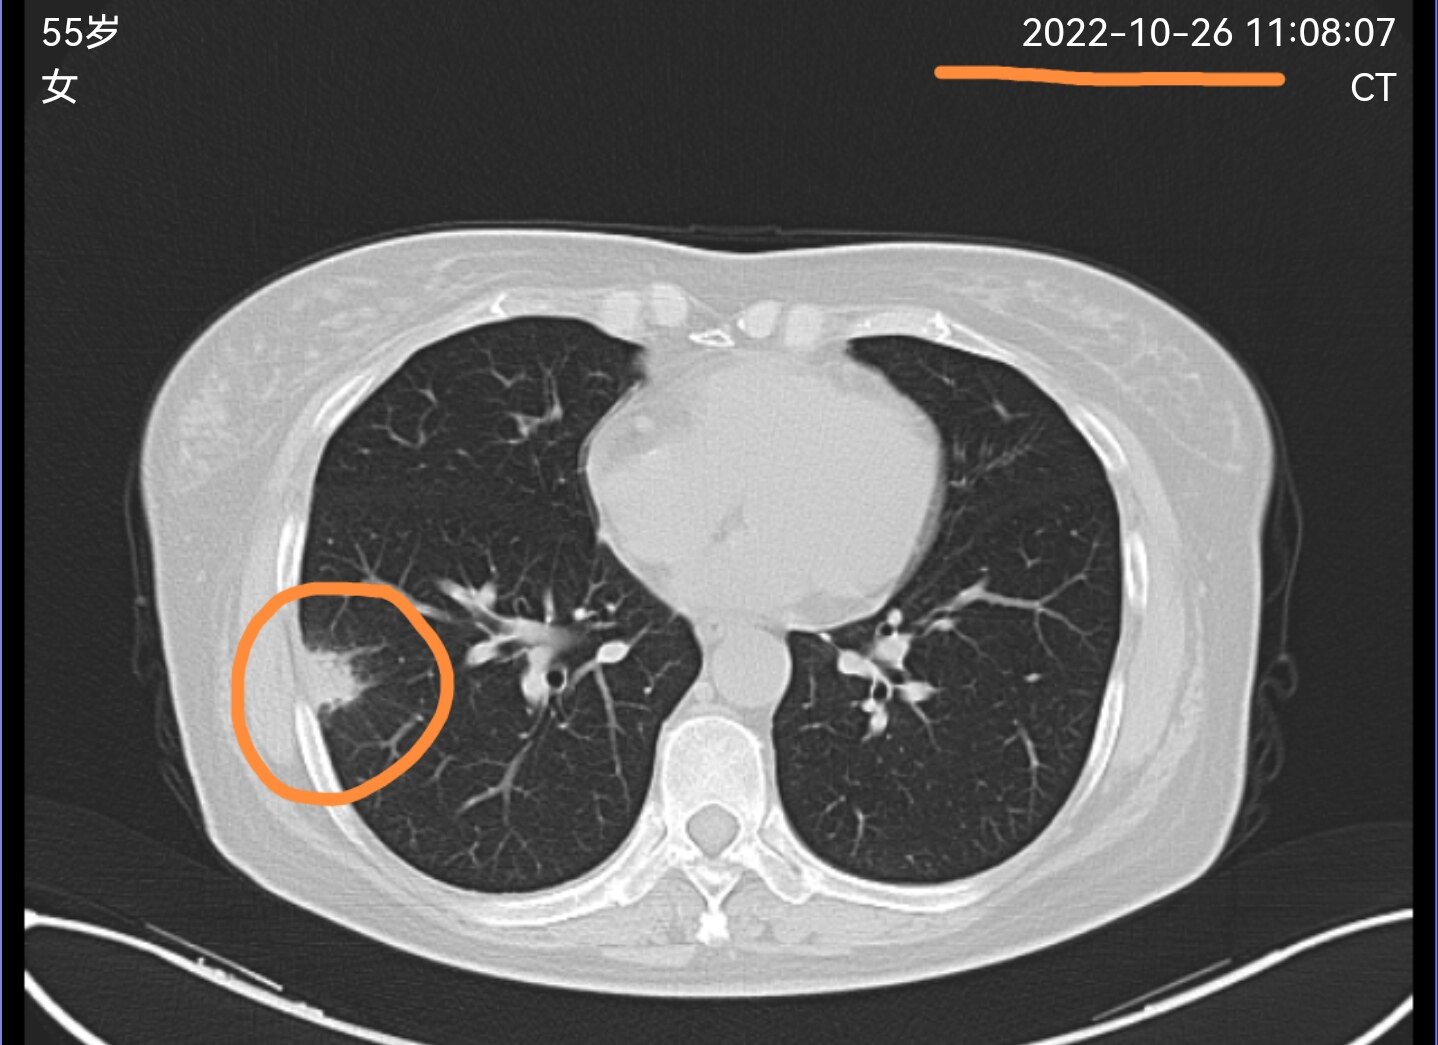

有一位东北的同行在线上门诊平台联系到我,把她这两个月拍的胸部CT电子图像发给了我。她10月底第一次拍片子时,发现了肺部靠近胸膜有一个结节,当地医生给安排了抗炎治疗,前两天她又复查了个CT,看到结节有变化了,想让我看一下结节的性质,还需不需要做手术?

从她第一次拍过来的片子看,这个肺结节首先考虑是一个炎性病变,当地医生安排抗炎治疗是完全正确的,五个星期之后再次复查,看到这一位置的这个结节较前明显消散,证实这是一个炎性结节,肯定不需要手术了。